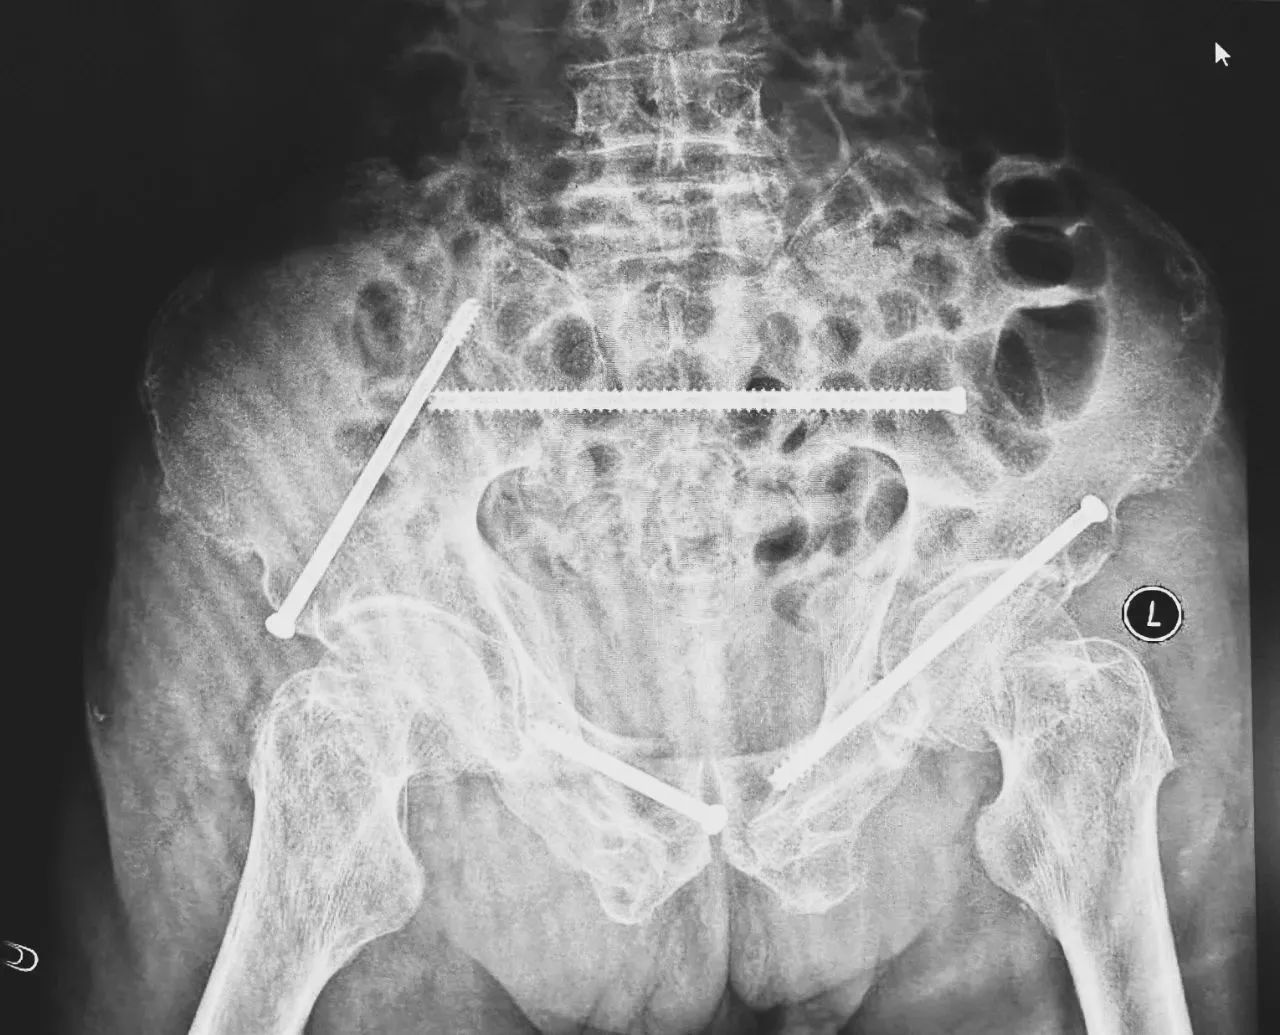

無影燈下,智能骨科團隊將患者示蹤器,放在左側髂前上棘,使用術中三維影像設備獲取骨盆的三維圖像,掃描結果傳輸至機器人導航系統,完成螺釘置入的位置和走形,并在機器人的引導下分別置入4枚通道螺釘。置入后再次進行CT掃描驗證,證實導針精確置入。

在骨科手術機器人毫米級精度的引導下,這項原本高難度、高風險的手術變得更加精準高效。手術共計耗時1個半小時,術中出血不到20毫升,每枚螺釘置入位置的切口長度約1.5厘米,完美達到了預期。術后,王大爺安全返回病房。

術后第二天,醫生團隊復查X片顯示螺釘植入位置非常滿意,骨折基本達到穩定復位,同時,復查的全血細胞計數中,血紅蛋白指數為102g/L。術后第三天,在智能骨科病房護理團隊及康復師的指導和護理下,王大爺可以坐立在床上。術后第四天,王大爺迎來了出院日,“得虧有了這么先進的醫療技術,讓我還能下地行走,謝謝你們!”

螺釘植入位置非常滿意